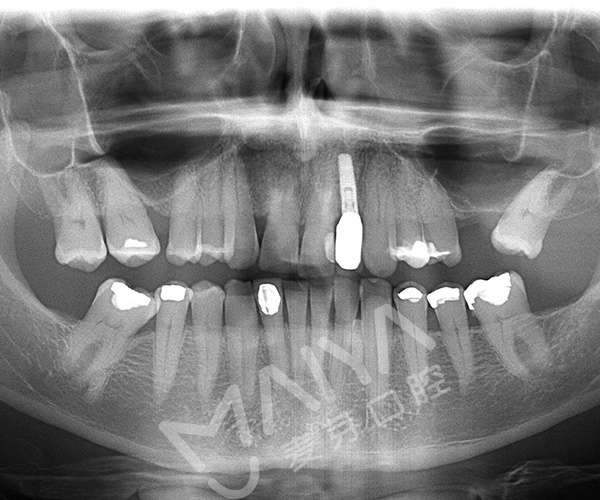

3D全景片权威分析

郑院长经过权威分析制定再次种植牙手术的种植方案,首先为Jack拔出患牙做了GPR植骨和保持位点手术,等四个月后缺牙部位形成很好的新骨,再次种牙。

种完牙的口腔全景片